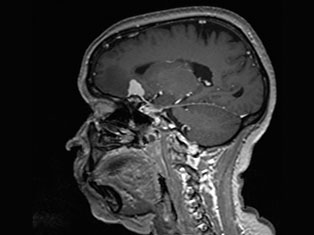

Brain Tumors

A brain tumor is a mass or growth of abnormal cells in your brain. Many different types of brain tumors exist. Some brain tumors are noncancerous (benign), and some brain tumors are cancerous (malignant).